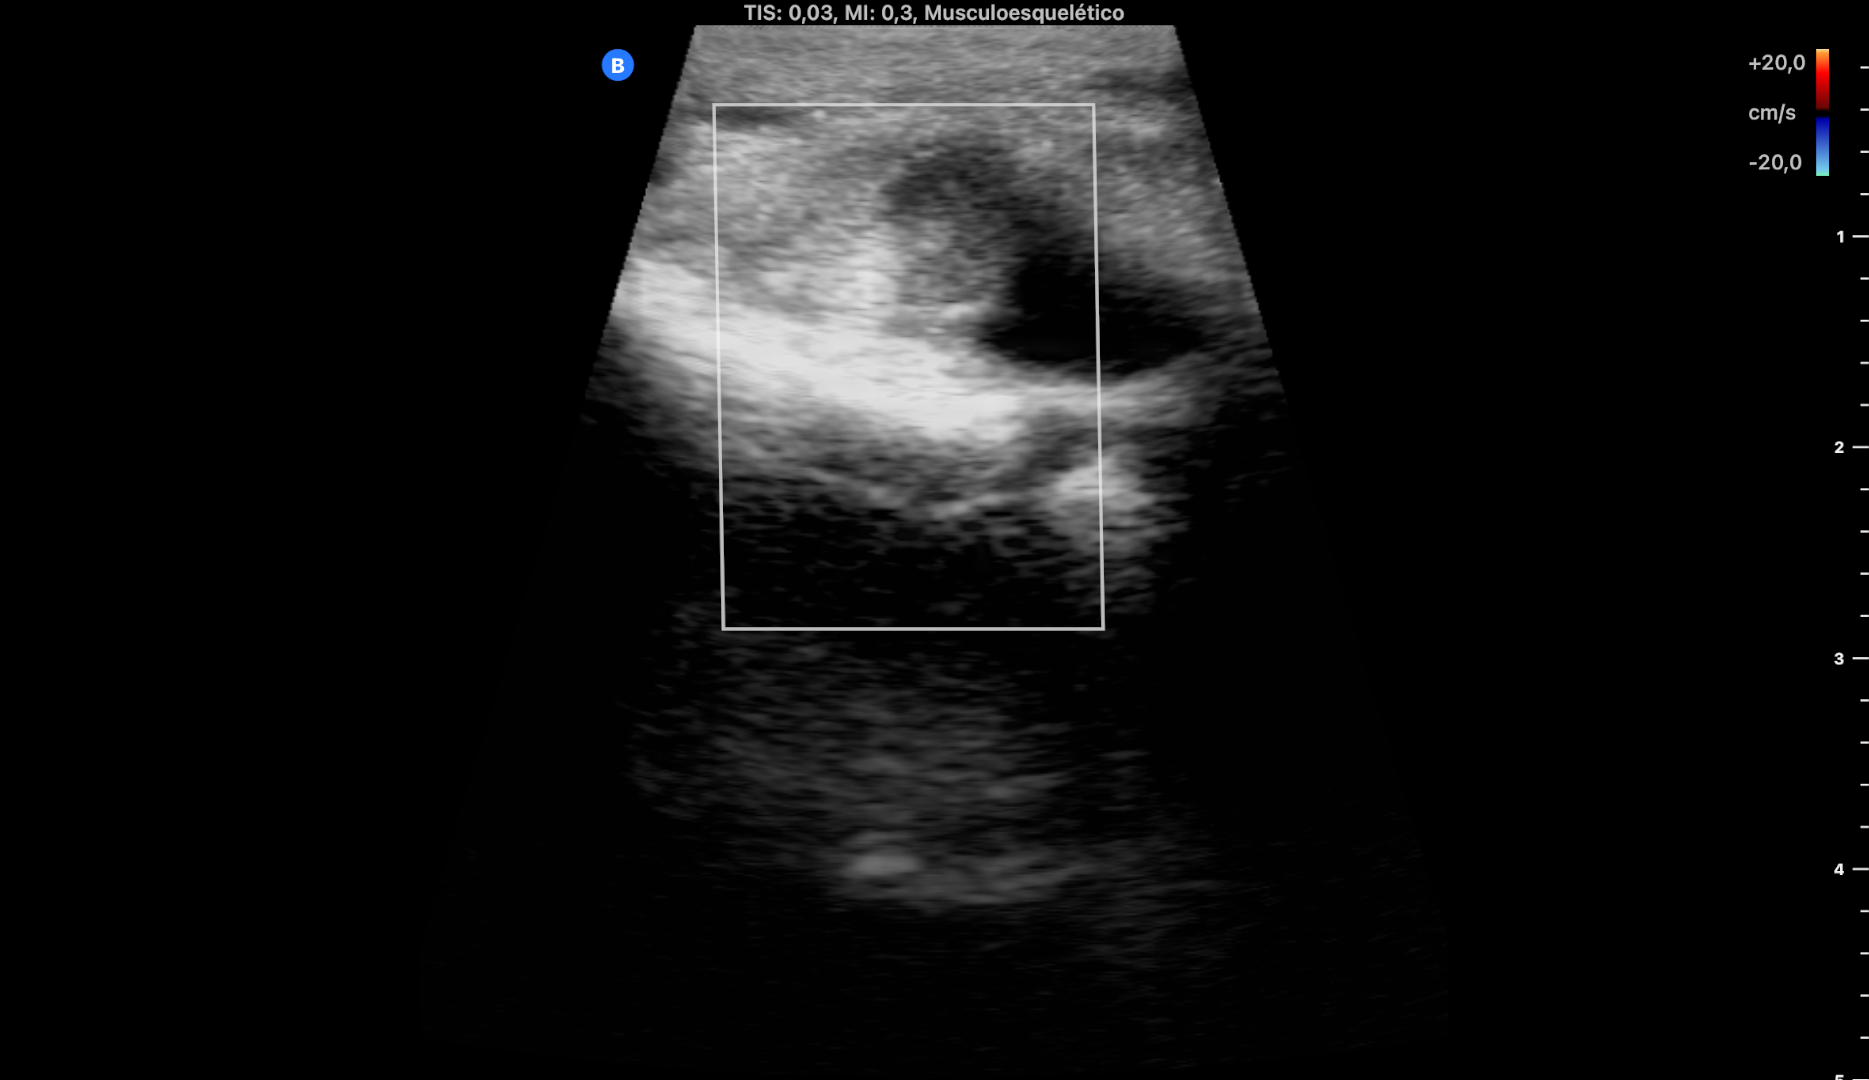

EcoAP: importantes dilataciones varicosas superficiales sin TVP en todo el recorrido de la pierna desde rodilla hacia tobillo. No TVP. No roturas fibrilares. Aquile íntegro.

A nivel del paquete de los tendones peroneos se objetiva importante tenosinovitis y desflecamiento del peroneo largo haciendo una imagen en boomerang.

Le pedí una ecografía reglada a fin de afinar el diagnóstico que confirmó mis hallazgos.

Impresión diagnóstica: tenosinovitis de la vaina del paquete tendinoso de los tendones peroneos a nivel de su paso retromaleolar.